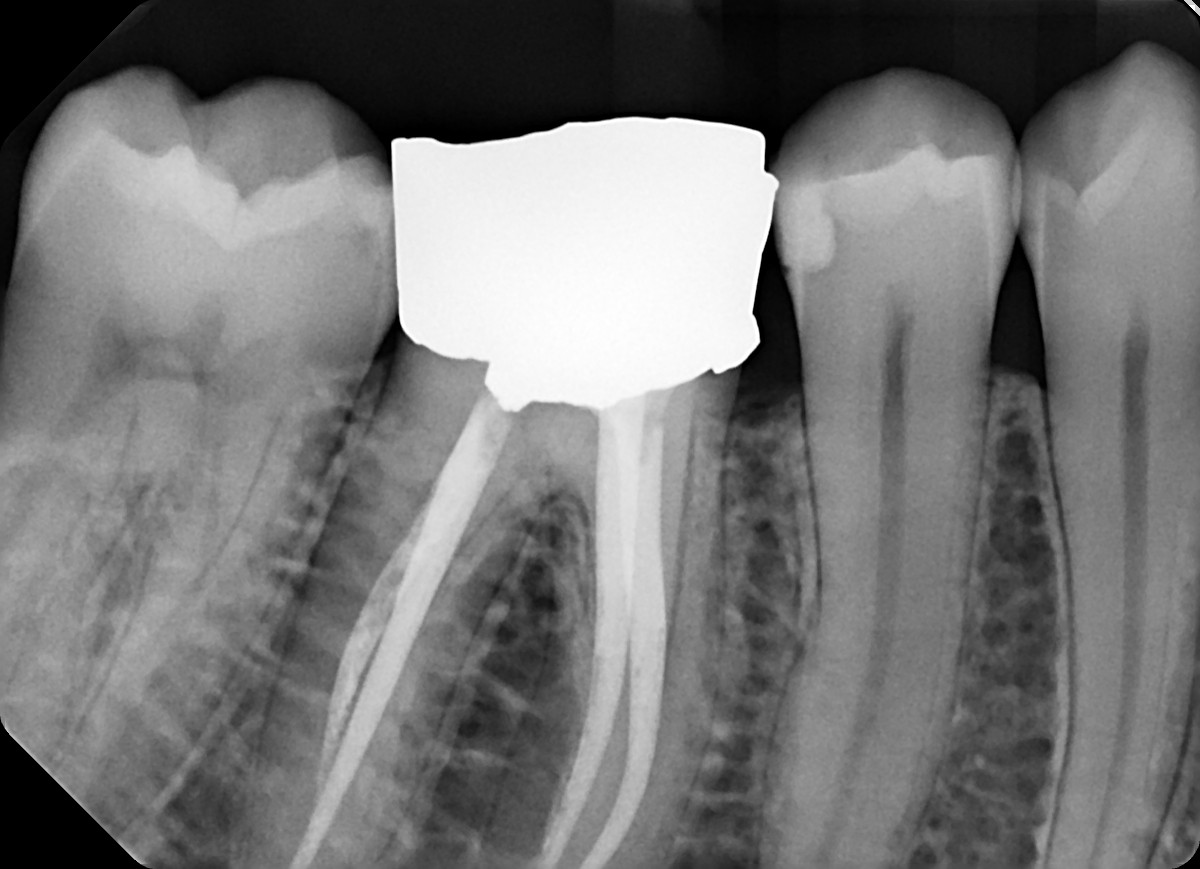

18. On which surface a recurrent caries can be detected?

crowns mostly show open margin not recurrent caries

19 / 35

19. On which surface a recurrent caries can be detected?

This is the PA X ray of the question # 18, based on this X ray recurrent X ray for distal tooth # 3.7 can also be selected